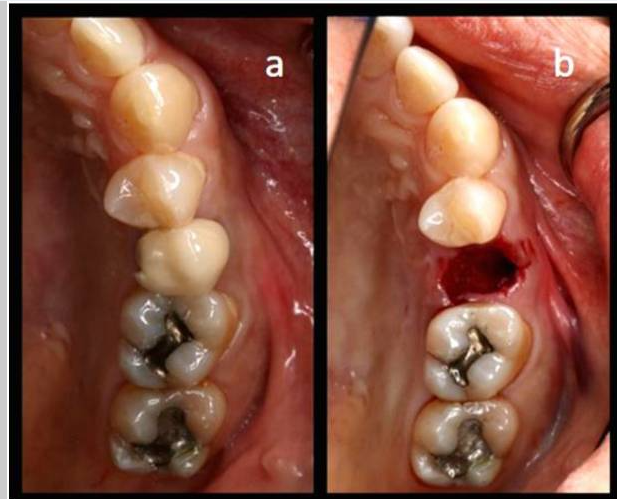

Case photos provided by: Clinical evaluation of 3D printed nano-porous hydroxyapatite bone graft for alveolar ridge preservation: A randomized controlled trial](Clinical evaluation of 3D printed nano-porous hydroxyapatite bone graft for alveolar ridge preservation: A randomized controlled trial - PMC)

Process diagram of clinical procedure; a) Cracked tooth #25; b) #25 Atraumatic extraction; c) Placement of HA hydroxyapatite granules in alveolar socket after atraumatic extraction, with closing of the socket by Cytoplast™ and suturing; d, e) After four months, harvesting of the grafted area with a trephine bur in formalin solution.